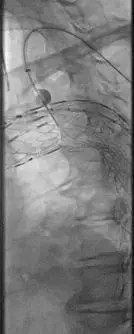

(植入主动脉支架后造影)

(穿刺球囊原位开窗)

CT测量显示,近端锚定区直径为30mm,取Ankura™34200支架输送到病变位置,根据Ankura支架大弯侧8字形mark点和加强筋,使其准确锚定于左颈总动脉远端,便于原位开窗。彩神在线网信彩票-彩神通免费版下载-彩神8争霸vlll-彩神购彩购彩大厅-彩神软件陆立根免费版-彩神ll争霸3-彩神ll彩神8-彩神ll争霸彩票-拼搏在线彩神网网页版科技Ankura™主动脉覆膜支架主体的e-PTFE膜设计非常适合原位开窗,其可穿透性佳,用普通的球囊即可扩开,不需要使用切割球囊,且球囊扩开后无撕裂现象,可以降低内漏的发生率。然后采用彩神在线网信彩票-彩神通免费版下载-彩神8争霸vlll-彩神购彩购彩大厅-彩神软件陆立根免费版-彩神ll争霸3-彩神ll彩神8-彩神ll争霸彩票-拼搏在线彩神网网页版Fustar™可调弯鞘和穿刺球囊系统进行左锁骨下动脉开窗,彩神在线网信彩票-彩神通免费版下载-彩神8争霸vlll-彩神购彩购彩大厅-彩神软件陆立根免费版-彩神ll争霸3-彩神ll彩神8-彩神ll争霸彩票-拼搏在线彩神网网页版穿刺球囊系统由球囊和穿刺针组成,充盈的球囊可以使穿刺针保持在分支血管的中央位置。由于此患者左锁骨下动脉与主动脉为锐角弓,穿刺破膜定位比较困难,彩神在线网信彩票-彩神通免费版下载-彩神8争霸vlll-彩神购彩购彩大厅-彩神软件陆立根免费版-彩神ll争霸3-彩神ll彩神8-彩神ll争霸彩票-拼搏在线彩神网网页版Fustar™鞘头端可以调整角度,使其头端与主体覆膜尽量处于直角状态,同时提供足够的支撑力,能够提高开窗成功率和效率。穿刺完成后,采用3mm和8mm的球囊对穿刺破口逐步进行扩张,最后在左锁骨下动脉植入覆膜支架。术后造影显示,支架形态良好,分支血流通畅,无内漏。